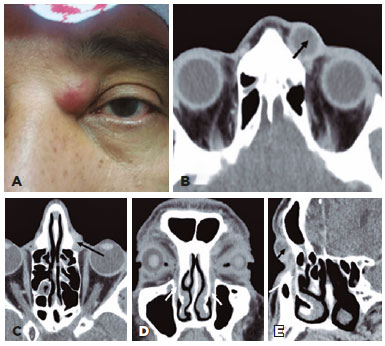

On examination, a firm painful mild erythematous tender mass was noted above the medial canthal tendon on the left side (Figure 1A). No abnormalities of the lacrimal puncta or spontaneous reflux were noted. The ocular exam was unremarkable bilaterally.

Computed tomography scan (CT scan) revealed the measurement of the left lacrimal sac as 1.6 cm × 1.3 cm × 2.3 cm and identified it as a well-defined marginally enhanced hypodense ovoid-shaped sac, filled with fluid-mucous secretion, enlarged just above the medial canthal ligament tendon, suggestive of acute dacryocystitis. The inflammatory reaction did not extend to the orbit. There was no dacryolith inside the lacrimal system. Coronal CT reformations of the axial images showed the entire course of the nasolacrimal ductus with funnel-shaped terminus juxta-lateral to the inferior nasal turbinate that was hypertrophic with a deviated bony nasal septum toward the left side (Figure 1B-E). Clinical treatment was started with 1 Gr oral amoxicillin and clavulanate potassium (Augmentin, SmithKline Beecham Ltd., Worthing, UK) and topical ophthalmic erythromycin ointment (erythromycin, API, Amman, Jordan) twice daily. One month later, the patient presented with a resolution of the acute dacryocystitis. The dye disappearance test was normal, regurgitation test was negative, and lacrimal syringing test indicated patency, suggesting an ADR diagnosis. Two years later, the patient was doing fine and had no more signs of inflammation in the lacrimal system.

CT scan was performed in our patient without contrast in the lacrimal system because the painful process at presentation prevented catheterization of the lacrimal system. However, it was possible to clearly observe the signs of acute dacryocystitis, a well-distinct image of the lacrimal sac enlarged just above the left medial canthal ligament tendon and toward in continuation with the nasolacrimal duct, with no dacryoliths.

Although CT scan is not routine to evaluate watery eyes, it provides excellent contrast resolution between bony structures and surrounding soft tissues, making it possible to observe the nasolacrimal duct within the bone channel in a funnel shape, soft tissue opacities (full opacity, partial opacity, or no opacity) reflecting air inside the lacrimal system, mucosal edema/thickening within the lacrimal system, and retention of secretions(10). Other drainage-limiting factors such as bony abnormalities, obstructive masses, and nearby anatomical structures are readily identified on CT scan, and observing these nasal alterations in our patient was decisive, such as hypertrophy of the inferior nasal turbinate with a deviated bony nasal septum toward the affected side, increasing the suspicion of nose alterations as the cause of temporary obstruction of the lacrimal system in our case.

CT scan in our case was also an important tool for ruling out other differential diagnoses such as dermoid cyst, encephalocele, or frontal sinus mucocele that usually presents in the upper internal quadrant of the orbit, superior to the medial canthal ligament tendon.